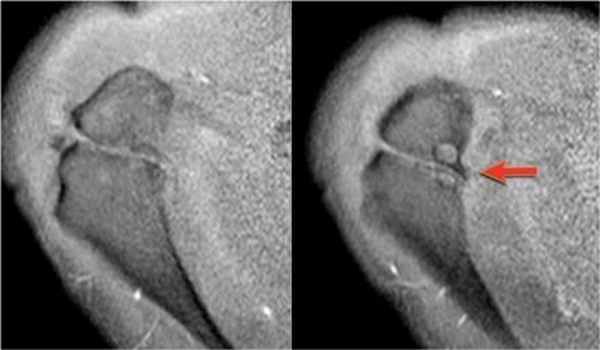

Вид в положении отведения и поворота плеча кнаружи (ABER)

Повреждения суставной губы

Изображения в положении отведения и поворота плеча кнаружи является наилучшим для оценки передненижних отделов суставной губы в положении 3-6 часов, где локализуется большинство ее повреждений. В положении отведения и поворота плеча кнаружи суставно-плечевая связка растягивается напрягая передне-нижние отделы суставной губы, позволяя внутрисутавному контрасту попасть между повреждением губы и суставной впадиной.

Повреждение манжеты вращателей

Изображения в положении отведения и поворота плеча кнаружи так-же очень полезны для кизуализации как частичных так и полных повреждений манжеты вращателей. Отведение и поворот конечности кнаружи высвобождает натянутую манжету больше чем при обычных косых корональных изображений в положении приведения конечности. В результате небольшие частичные поврждения волокон суставной поверхности манжеты не прилегают ни к интактным пучкам, ни к головке плечевой кости, и внутрисуставной контраст улучшает визуализацию повреждений (3).

Изображения в положении отведения и поворота плеча кнаружи получаются в аксиальной плоскости путем отклонения на 45 градусов от коротальной плоскости (см. иллюстрацию).

В этом положении область на 3-6 часов ориентирована перпендикулярно.

Обратите внимание на красную стрелку указывающую на небольшое повреждение Пертеса, которо не визуализировалось при стандартной аксиальной ориентации.